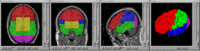

- BRAINS Auto Workup - Fully automated image analysis pipeline for generation of volumetric measurements. NITRC Link

- BRAINS Gallery